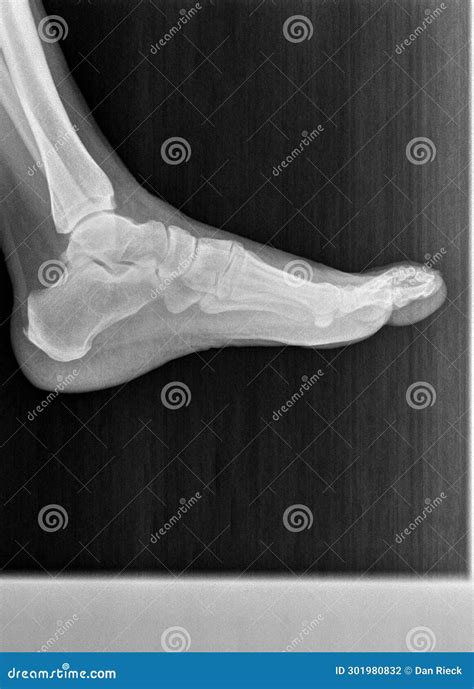

A Lateral Foot X Ray is a type of radiographic imaging that captures a side view of the foot. This view is essential for evaluating the alignment and integrity of the bones, joints, and soft tissues in the foot. Unlike an anteroposterior (AP) view, which provides a front-to-back image, a lateral view offers a different perspective that can reveal issues not visible in other projections.

• Bone Alignment: It helps assess the alignment of the foot bones, which is crucial for diagnosing conditions like flatfoot or high arches.

• Fracture Detection: It can detect fractures that may not be visible in other views, especially in the calcaneus (heel bone) and metatarsals.

• Joint Assessment: It provides a clear view of the joints, helping to identify arthritis, dislocations, or other joint-related issues.

• Soft Tissue Evaluation: While primarily used for bone evaluation, it can also show soft tissue abnormalities, such as swelling or foreign bodies.